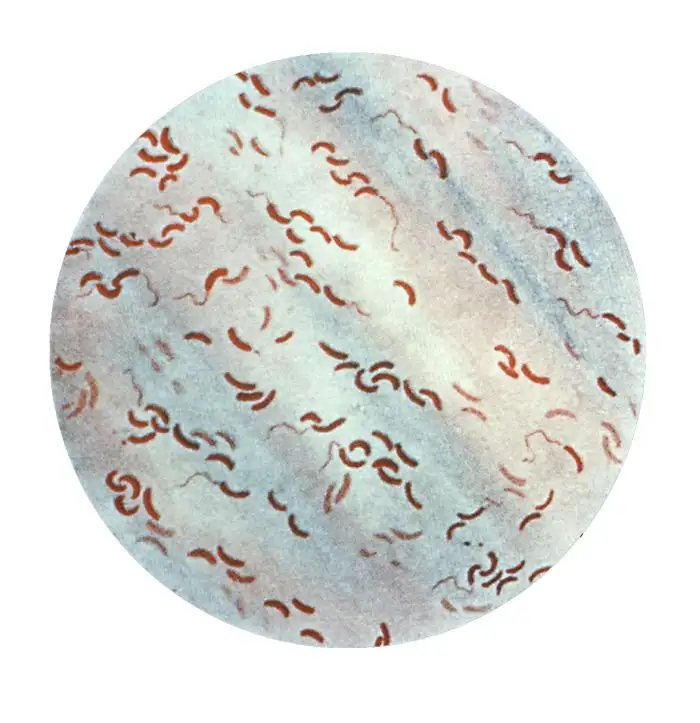

讽刺的是,就在斯诺在伦敦绘制他的死亡地图的同时,一位意大利显微学家菲利波·帕奇尼正在佛罗伦萨进行着另一项同样具有开创性却被完全忽视的工作。帕奇尼使用显微镜检查霍乱死亡者的肠道组织,发现了一种前所未见的微生物——一种微小的、逗号形状的细菌。他将这种生物命名为"弧菌",并在1854年发表了一系列论文,详细描述了这种细菌与霍乱之间的关系。然而,当时医学界的主流观点仍然顽固地坚持瘴气说,帕奇尼的发现被完全忽视了。他孤独地继续着自己的研究,直到1883年在贫困中死去。直到几十年后,科学界才承认了帕奇尼作为霍乱病原体发现者的地位。1966年,国际细菌学命名委员会正式将霍乱病原体命名为"霍乱弧菌帕奇尼",以纪念这位被遗忘的科学先驱。

1883年,德国细菌学家罗伯特·科赫前往埃及和印度调查霍乱疫情。在亚历山大港和加尔各答的实验室里,科赫独立地"重新发现"了帕奇尼二十多年前就已经描述过的逗号形细菌。科赫成功地在纯培养中分离出了这种细菌,并详细描述了它的形态特征。他在给德国政府的报告中写道:这是一种略微弯曲的杆菌,像逗号一样,它在肠道粘液中大量存在。科赫的发现很快得到了广泛认可,他因此获得了1905年的诺贝尔生理学或医学奖。而帕奇尼的贡献,则几乎被历史完全遗忘,直到二十世纪后期才被重新发现和承认。

霍乱弧菌是一种极其狡猾的病原体。它的外形像一根微小的逗号,通常只有1.5到2微米长,0.5微米宽。在显微镜下,它们看起来像一群活泼的小鱼,依靠一根长长的鞭毛在液体中高速游动。当这种细菌通过污染的水或食物进入人体后,它们会在胃酸的屏障下损失大部分,但少数幸存者会进入小肠,那里温暖、潮湿、富含营养的环境为它们提供了理想的繁殖场所。在抵达小肠后的几小时内,这些细菌会迅速增殖,每二十分钟就能翻一番。一个霍乱患者在腹泻高峰期,每毫升肠液中可能含有超过一亿个细菌。